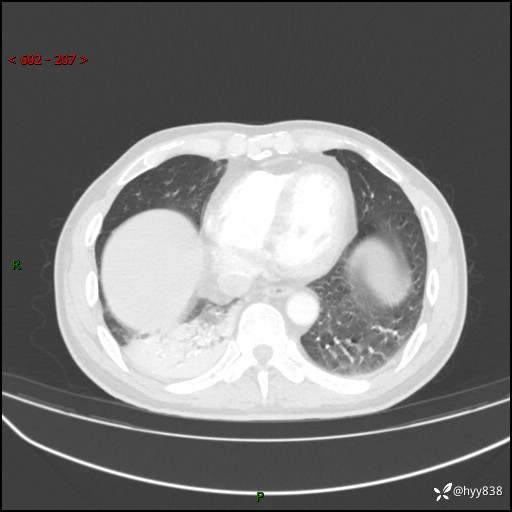

63岁/男,发热5余天。精彩好病例,“大叶性肺炎”,等你来诊---结果公布~

【患者信息】:63岁/男

【主诉】:发热5余天

【现病史及既往史】:患者5余天无明显诱因出现畏寒寒战发热,最高体温39.5℃,发热无明显昼夜规律,伴全身乏力、头晕,无头痛、无咳嗽咳痰、无胸痛咯血、无气短、无腹痛腹泻、无尿频尿急尿痛等不适,于当地市第五人民医院就诊,予以抗感染等治疗(具体不详)后发热无明显好转,1天前查胸部CT提示右下肺感染,为求进一步诊治,门诊以“社区获得性肺炎”收治入院; 起病以来,患者精神、食欲一般,睡眠可,大小便正常,体力体重较前无明显变化。

【检查】:胸部CT增强